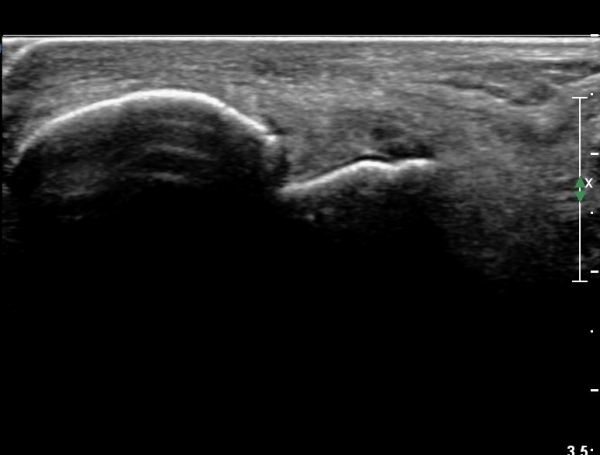

Àü°ÅºñÀδë Á¾´Ü¸é°Ë»ç¿¡¼­  Àü°ÅºñÀδëÀÇ ÆÄ¿­À» º¸ÀÓ(»çÁø 2).